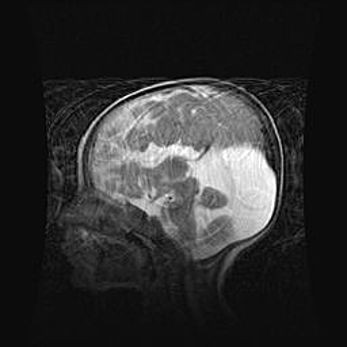

Мальформация Денди-Уокера. Киста задней черепной ямки.

Агенезия мозолистого тела.

Возраст: 2,5 месяца

Вес: 2420 г

Пол: женский

Окружность головы: 37 см

Срок гестации: 32 недели

Мальформация Денди—Уокера — редкий вид патологии ЦНС, представляющий собой врожденный порок развития каудального отдела ствола и червя мозжечка, ведущий к неполному раскрытию срединной (Мажанди) и латеральных (Лушка) апертур IV желудочка мозга. Для этогно синдрома характерна триада симптомов: гипотрофия червя мозжечка и/или полушарий мозжечка, кисты задней черепной ямки, гидроцефалия различной степени. В 70% случаев порок сочетается и с другими аномалиями головного мозга, в частности с агенезией мозолистого тела.